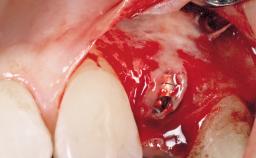

Immediate Placement of an Implant in a Maxillary Right Central Incisor Site

A 30-year-old female patient was referred to the office for the treatment of tooth 11. Her chief concern at the initial visit was to inquire, “Why is my tooth pink?” Upon clinical examination, it was determined that tooth 11 had a previous history of trauma and that the clinical crown had become noticeably pink in color as a result of internal resorption. This diagnosis was confirmed radiographically, indicating a large radiolucency involving the central and distal portions of the clinical crown. It was determined that restoration of this tooth was not possible, and that extraction was indicated. The presence of a mid-line diastema, which the patient wanted to reproduce, directed the treatment plan for tooth replacement utilizing a dental implant.

Type of Implants One-Piece|Reduced-Diameter

Placement Protocol Immediate implant placement

Socket Morphology Single-root socket

Socket Integrity Sufficient, with intact bone walls